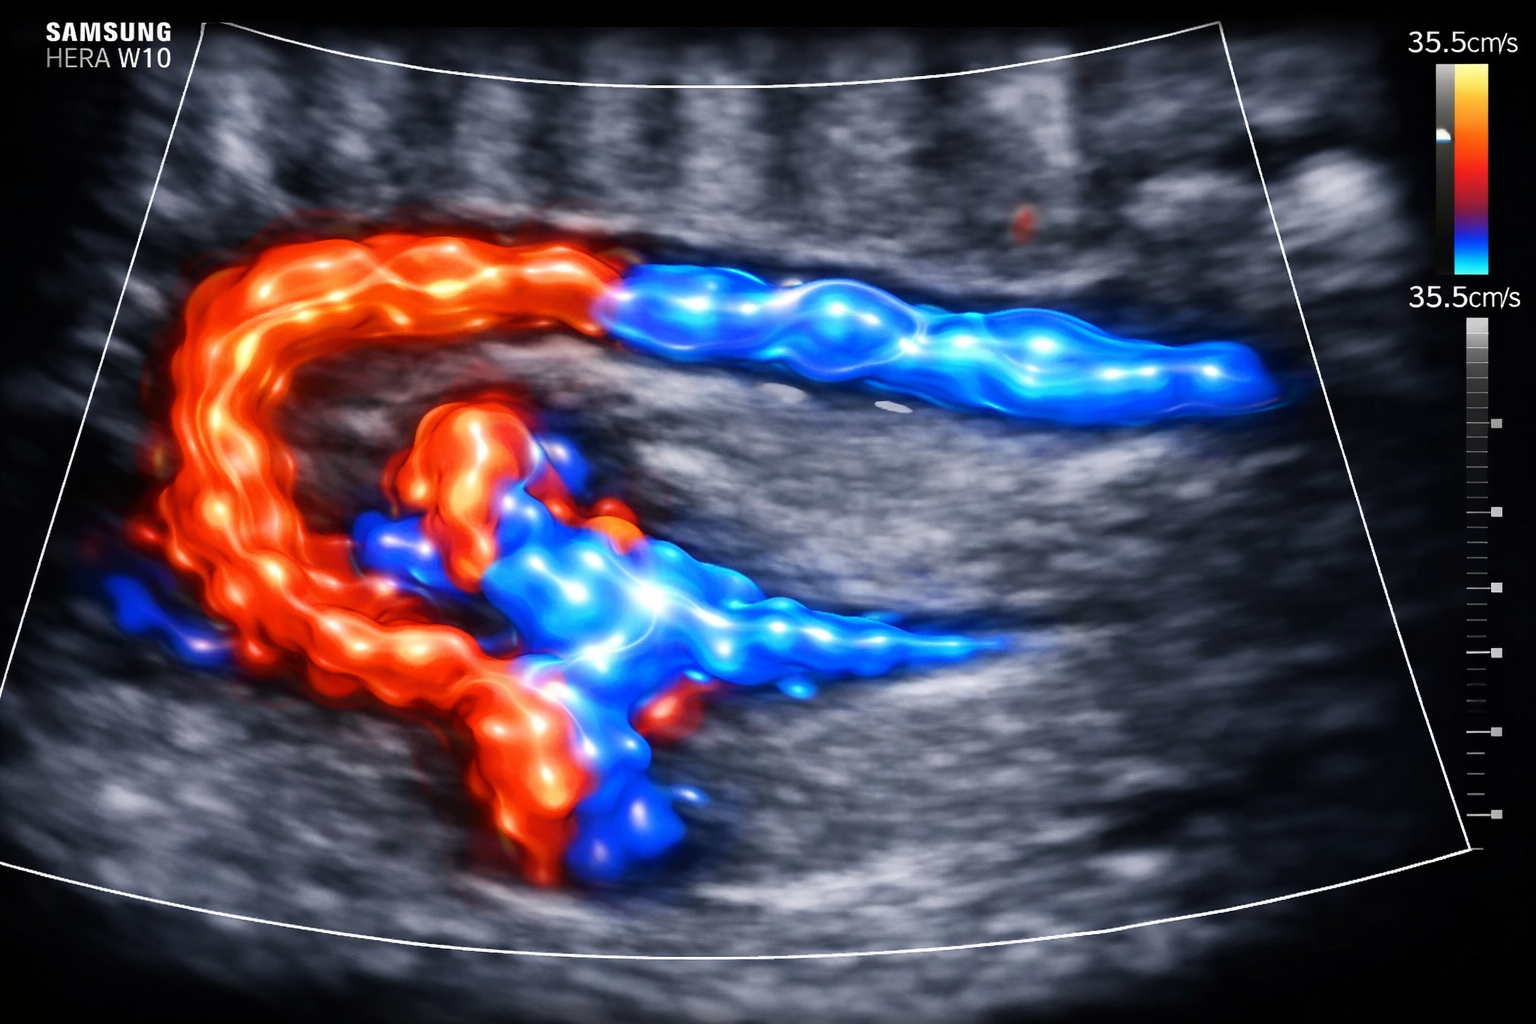

O exame Doppler vascular permite avaliar o fluxo sanguíneo em artérias e veias com análise técnica detalhada. Além disso, auxilia na identificação de obstruções, tromboses e outras alterações circulatórias. Dessa forma, contribui para um diagnóstico mais preciso e para a definição da melhor conduta clínica.

Mapeamento Hemodinâmico

Utiliza Doppler colorido e espectral para avaliar velocidade, padrão de onda e repercussão funcional. Assim, as alterações encontradas podem ser melhor caracterizadas.

Realizamos o exame com equipamentos de alta definição, análise em tempo real e protocolo técnico direcionado ao território vascular estudado. Dessa forma, a avaliação ocorre com precisão e consistência diagnóstica.